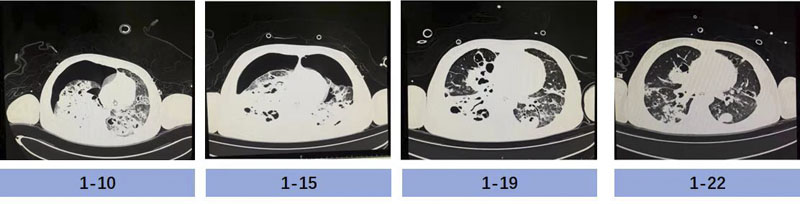

成功撤離ECMO,只是“生命闖關”的第一步,如何控制感染、恢復肺功能、脫離呼吸機支持、避免院內感染及獲得性肌無力,是醫護人員面對的又一個難題。根據基因測序及培養結果回報,患兒血液及肺泡灌洗液標本中均檢出大量金黃色葡萄球菌(基因序列數高達一百多萬條)及流感嗜血桿菌(基因序列數高達二十多萬條),兩者疊加,破壞力巨大;患兒肺部影像學提示:雙肺大面積實變、滲出及空洞,極易引發自發性氣胸。

胡振杰主任臨床經驗豐富,在病原學結果回報之前就判斷患兒金黃色葡萄球菌感染可能性大,結合迅速發展的多臟器功能衰竭癥狀,第一時間應用了廣譜抗生素(美羅培南聯合利奈唑胺)抗感染治療。隨著藥敏結果回報,金黃色葡萄球菌為敏感菌株,指南推薦甲氧西林敏感的金葡菌(MSSA)肺炎首選抗葡萄球菌青霉素類與一代頭孢,而甲氧西林耐藥的金葡菌(MRSA)肺炎首選萬古霉素、利奈唑胺。考慮到患兒并不是單純的MSSA肺炎,合并血流感染及多臟器功能衰竭,并且對頭孢類藥物過敏,抗生素選擇應精準且符合實際,斟酌再三,胡振杰主任毅然選擇了單純應用哌拉西林他唑巴坦抗感染治療,一定程度上避免了廣譜抗生素導致的耐藥菌發生。為更好地改善患兒肺部通氣不均一性,醫護人員協助患者行俯臥位通氣治療,密切監測肺部體征和影像學評估,第一時間發現氣胸并緊急請胸外科醫師為患兒行胸腔閉式引流術,反復調整引流管位置,給予負壓吸引,進一步促進肺泡擴張。